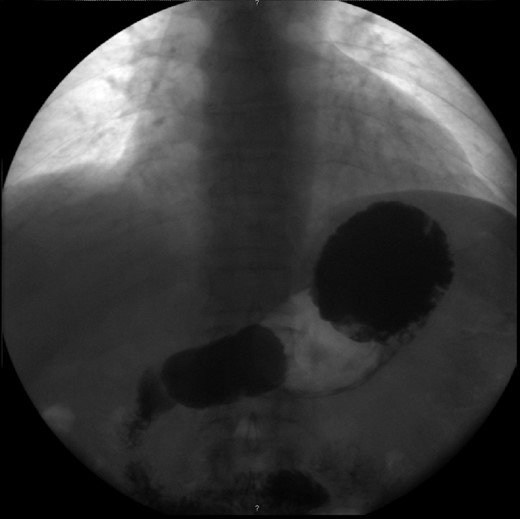

Haematological and biochemical profiling were performed, as well as plain abdominal radiographs (Fig. 4) and abdominal ultrasound, all showing no relevant changes. The upper endoscopy revealed a mild esophagitis. An upper gastrointestinal series was later executed, revealing the presence of an organoaxial volvulus (Fig. 5).

Abdominal radiograph performed during a symptomatic interval, showing no relevant changes.